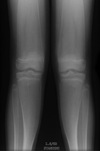

Give 3 differentials in order of likelihood.

(Erlenmeyer flask deformity) 1. Thalassemia 2. Sickle cell anemia 3. Osteopetrosis

44

Give 2 differentials in order of likelihood.

1. Thalassemia 2. Sickle cell anemia